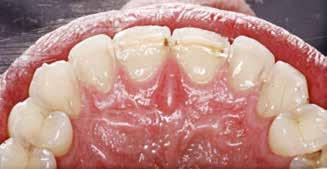

ABSTRACT

BAGGRUND – Denne kasuistik beskriver en patient, hvor der blev valgt protetisk behandling i ung alder.

PATIENTTILFÆLDE – En niårig pige havde stort behandlingsbehov og smerter fra tænderne på grund af tandudviklingsforstyrrelse. Der var flere gange forsøgt restaurering med komposit, som ikke fungerede. Laminater i feldspatkeram blev valgt for at fjerne mindst mulig tandsubstans, øge holdbarheden på restaureringerne og forbedre æstetikken. Patientens motivation, meninger og kooperationsevne var vigtige for behandlingsvalget, da behandlingen var tidkrævende og til tider udmattende for en ung patient.

KONKLUSION – Resultatet var vellykket og medførte forbedret livskvalitet. Protetisk behandling med adhæsiv teknik kan være et godt behandlingsalternativ for børn og unge på ret indikation.

EMNEORD Adhesives | amelogenesis imperfecta | ceramics | pediatric dentistry | quality of life

Protetisk behandling med adhæsiv teknik –et alternativ i ung alder?

Klinisk undersøgelse viste emaljehypoplasier og hypomineralisering på 1+, +1, 2-, 1-, -1 og -2 (Fig.1). Hun havde Angle klasse II, pladsmangel i begge kæber og agenesi af -5. Der var isninger ved spisning og tandbørstning. Fundene var forenelige